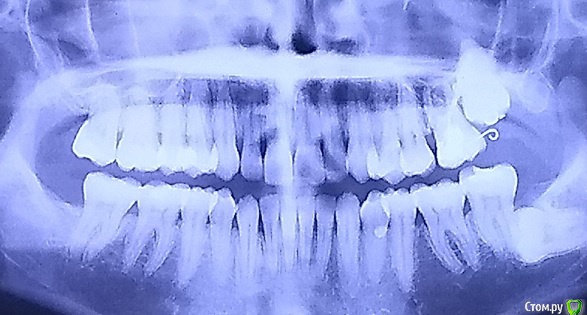

sus Опубликовано 13 декабря, 2016 Поделиться Опубликовано 13 декабря, 2016 (изменено) Здравствуйте, уважаемые специалисты! Пожалуйста, помогите принять решение, хирургия назначена на пятницу. Возраст - 32. Имеется импактированная семерка, которую сейчас хотим удалить. Раньше надеялись, что она спустится сама после удаления восьмерки в 2012 (она еще есть на первом, старом, фото), плюс поможем брекетами. За это время она сама так и не спустилась, так что ортодонт и хирург предположили анкилоз и отсутствие возможности вытянуть ее, даже сломав "мостики" и потянув брекетами. Единственная причина удаления - это торчащий над слизистой кусочек коронки, и, соответственно, в перспективе риск инфицирования через карманы вокруг. По томограмме, наверное, видно, что сам зуб пока вроде здоров (а торчит он так уже лет двадцать). Только что сделали томограмму, вот такие результаты - однозначно анкилоз, luxation (разрушение "мостиков") сделать не получится, очень большой контакт. Хирург говорит, что для него опция номер один - это полное удаление, но есть шанс перфорации синуса и необходимости повторной операции, если "подлатывание" в процессе удаления не поможет (он хотел что-то положить туда, забыла, коллаген, что ли). Второй вариант - коронэктомия. Мне по прочтении ряда статей показалось, что это как раз самый популярный и безопасный способ решения в такой ситуации. Но хирург уверяет, что оставшиеся корни вполне могут инфицироваться, а через них - и синус, и он бы предпочел делать так только в ситуации невозможности удалить зуб целиком (если он слишком крепко "прирос"). Но можно и сделать так, если я хочу, поскольку это более консервативно. Итак, что мне выбрать? Или при таких рисках вообще не трогать его? Праздники впереди, опять же - я рассчитывала на менее травматичное удаление коронки или luxation.И бонусом академический вопрос, неужели зуб мог так прирасти за четыре года (если хирург, подергав его после "вскрывания" при удалении восьмерки в 2012, утверждал тогда, что у зуба нормальная мобильность). Мне казалось, что "прирастание" должно происходить на более ранних стадиях развития.Очень хотела бы все понять как можно раньше, до встречи с доктором. Спасибо вам большое за внимание! Изменено 13 декабря, 2016 пользователем sus Ссылка на комментарий

sus Опубликовано 14 декабря, 2016 Автор Поделиться Опубликовано 14 декабря, 2016 (изменено) Нет, этот зуб не выдвигали. В 2012 мне удалили эту восьмерку и заодно вскрыли фолликул, по выражению хирурга, над этой семеркой. Хирург попробовал пошатать, сказал, мобильность нормальная, и зашил. Ортодонт обещал после курса Invisalign надеть на меня брекеты, чтобы получить идеальный результат, а также прицепить к ним эту семерку. Собственно. поэтому я его выбрала, другие два ортодонта утверждали, что эта семерка тоже под удаление. Год назад, когда речь защла о переходе на брекеты, ортодонт сказал: "Да она совсем не опускается, значит, анкилоз. Если я ее потащу брекет-системой, я утоплю шестерку, а семерку все равно не вытяну. Так что этого делать ни в коем случае не будем. Переместить ее с блоком кости тоже не получится, вотому что мы перфорируем синус. Если мы сделаем luxation, то он тут же прирастет обратно. Если помле освобождения тут же его переместить в желаемую позицию и закрепить там брекетами, он не прирастет (слишком большое расстояние). Можно сделать коронэктомию, как хирург решит". Потом он посоветовался с опытным университетским хирургом, провел конференц-звонок с моим хирургом и основным дантистом, и они решили, что нужно удалять, никакие методы ортодонтии тут не имеет смысла применять. А в итоге оказалось после вчерашней встречи и томограммы, что все равно удалять целиком и перфорировать синус, чего я надеялась избежать. Вы согласны, что с блоком двигать в такой ситуации нереально? Будет яма на дне синуса? Моя-то голубая мечта с детства - поставить уже этот зуб на его законное место (хотя полезного контакта он даст всего порядка 2 мм). Ну, это мой бзик - лечиться-чиниться Изменено 14 декабря, 2016 пользователем sus Ссылка на комментарий

Bier Опубликовано 17 декабря, 2016 Поделиться Опубликовано 17 декабря, 2016 во первых перфорация синуса не помеха для хирургического выдвижения зуба, грамотный ортогнатический хирург способен на это. В Новосибе не знаю, но в стране есть такие специалисты.Во вторых досужие рассуждения не говорят, что зуб анкилозирован, скорее всего это не так. Можно применить стабилизацию опорных зубов миниимплантатами, тогда опасаться можно не опасаться что они "поедут". Если зуб можно раскачать - это 100% не анкилоз и ничего назад не прирастет. Если не прибегать к ортогнатической хирургии, то мой план лечения такой: стабилизация 26 миниимплантатом, люксация 27з, ортодонтическая нагрузка. Вангую, что зуб выйдет за 3-4 мес. И только, если люксация зуба невозможна можно говорить об удалении или коронэктомии. 1 Ссылка на комментарий

sus Опубликовано 21 июня, 2018 Автор Поделиться Опубликовано 21 июня, 2018 (изменено) И снова здравствуйте, дорогие доктора. Итак, мы сделали все по плану, описанному выше. Мне поставили TAD на трех шурупах (между 27 и 26), к нему примотали 26, на 26 надели пояс с торчащей проволокой, к ней примотали резинкой крепление на 27 (после его лаксации). Во время лаксации я слышала/чувствовала немного хруста, но было ощущение, что зуб и челюсть составляют единое целое Под нагрузкой я проходила с января по май. В результате 27 не сдвинулся с места, 26, несморя на защиту, повернулся (оно и понятно, такие уж там углы воздействия) - см. фото, плохое, но, наверное, сейчас это не очень важно. Теперь и хурург, и ортодонт уверены, что ничего сделать нельзя, зуб анкилозный. Ортодонт говорит, что в его практике такие зубы никогда не двигались. Хирург сказал, что я, конечно, могу поискать другого спеца, который, возможно, сможет выдвигать зуб с блоком кости, а он не может туда подступиться (с одной стороны, для доступа с окклюзионной стороны нужен открытый рот, с другой, при опущенной челюсти сустав блокирует область доступа (у меня вообще очень маленькие челюсти и рот). Я предложила лаксировать еще раз, более агрессивно. Но он не верит, что еще одна лаксация поможет, зуб, мол, и должен ощущаться как единое целое с челюстью, иначе это уже называется удаление, и поcле такого активного воздействия зуб просто выпадет, если его не зафиксировать в прежнем положении, и тогда из-за травмы он тут же намертво прирастет. Так что у меня сейчас варианты 1) со всей этой конструкцией обратиться к хирургу в Новосибирске (я все равно туда еду), чтобы мне или "перелаксировали", или выдвинули хирургически 2) все снять и удалить зуб а) целиком б) коронэктомией 3) все снять и оставить зуб в покое, следя за его состоянием (к дантисту хожу по графику, рентген тоже регулярно по стандарту). Что посоветуете? Неужели нет надежды ( Спасибо большое! Изменено 21 июня, 2018 пользователем sus Ссылка на комментарий